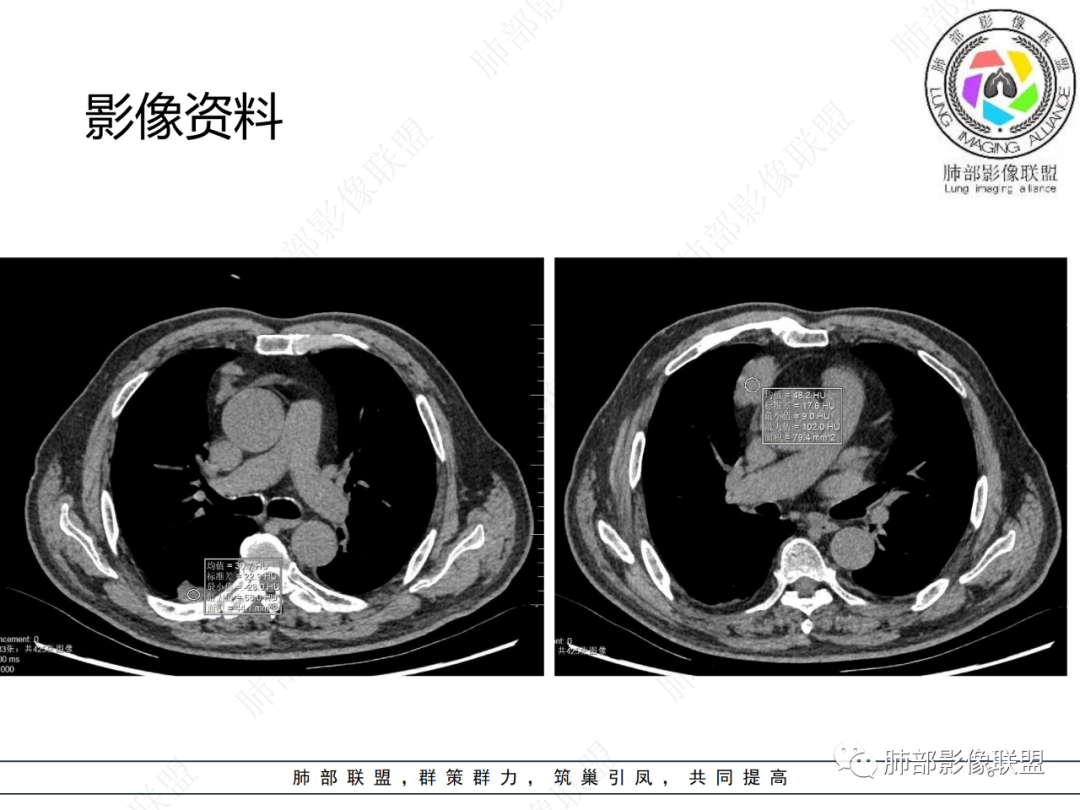

老年男性,体检发现纵隔占位,胸部CT检查所见,前纵隔多发软组织结节或肿块,右侧胸膜结节,密度均匀,边缘分叶,未见明显坏死,强化尚明显均匀强化,冠状位第1张图,左侧膈肌连续性中断,未见明确脾脏显示,可以考虑转移?异位组织(异位脾脏)?如果左侧膈肌确实断裂且无脾脏那么考虑异位脾脏可能大,或者代偿的淋巴结,再有鉴别神经源性肿瘤,入鞘瘤,不过鞘瘤一般会有ab区,这个病例没有。

右前纵膈不规则软组织密度影,密度均匀,分叶,中度强化,心包受侵,右侧胸膜不规则结节,明显强化,考虑胸腺瘤B2或B3型伴胸膜转移,鉴别胸腺癌

老年男性,前纵隔软组织结节灶,分叶状,偏于右侧,右侧胸膜亦可见结节灶,考虑高危型胸腺瘤或胸腺癌侵及胸膜

老年男性,右前纵隔结节,右侧胸膜下小结节,增强前纵隔结节中度欠均匀性强化,首先考虑胸腺瘤(B2、3级),鉴别纵隔神经内分泌肿瘤,比如类癌。

男,76岁,前纵膈偏右结节,形态较规则,浅分叶,富血供,增强明显不均匀强化,强化峰值在动脉期,考虑B2,3胸腺瘤,鉴别胸腺类癌(一般强化峰值在静脉期),胸腺鳞癌(形态不规则,边缘不清晰,多侵犯邻近大血管)

肺盟病例,右前纵膈占位,边缘有钙化,强化显著,临近心包有少许积液。考虑胸腺类癌可能,右肺胸膜下病灶考虑炎性肉芽肿可能。